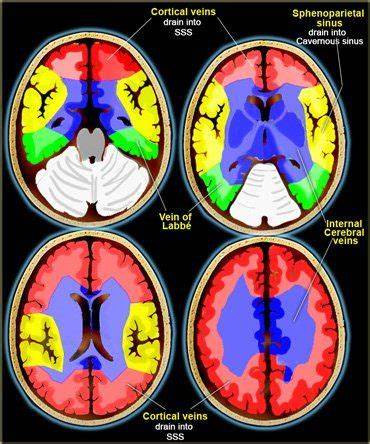

• Cerebral Veins 🧠